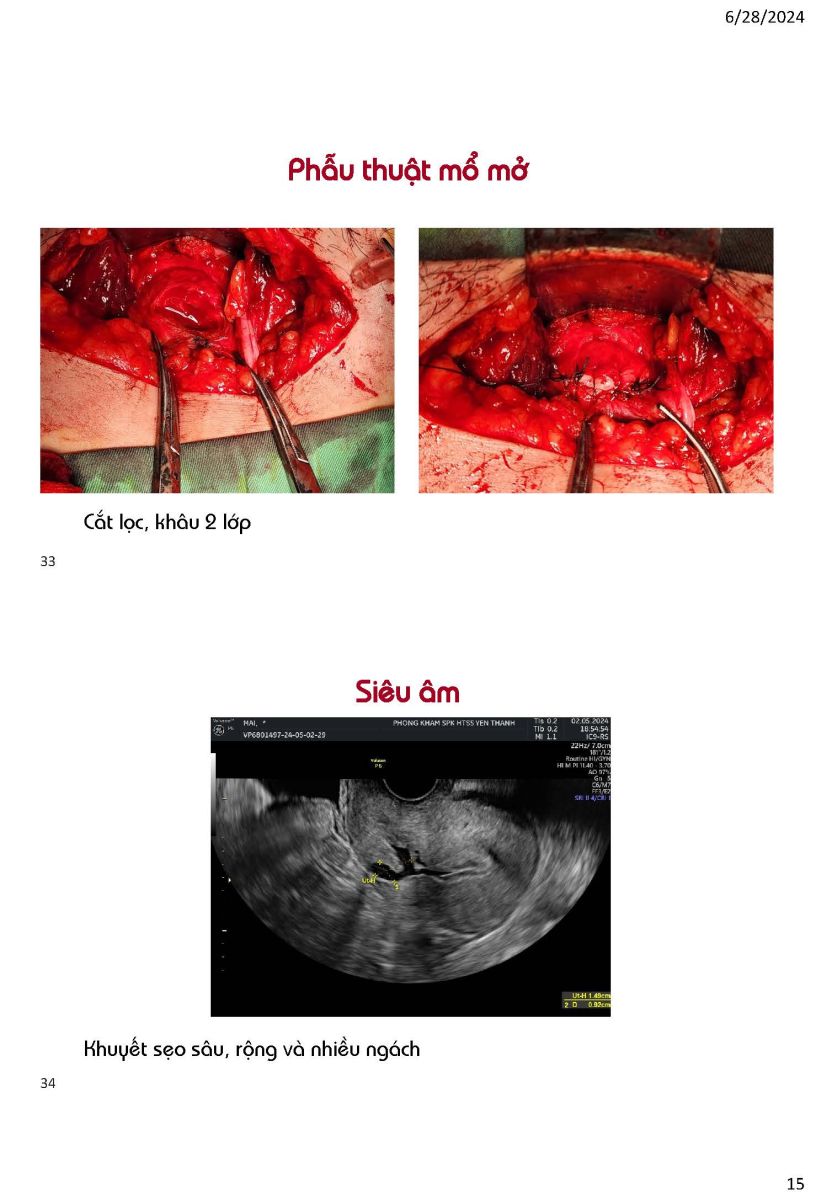

Ứng dụng siêu âm trong quyết định phương pháp can thiệp khuyết sẹo mổ lấy thai